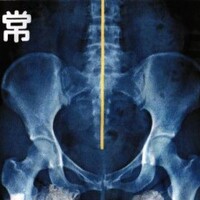

子宮・卵巣の機能は骨盤と深く関連する骨盤の歪みがあると、妊娠しにくくなる可能性があります。 歪みによる影響 仙骨矯正(骨盤矯正) 歪んでしまった仙骨が […]